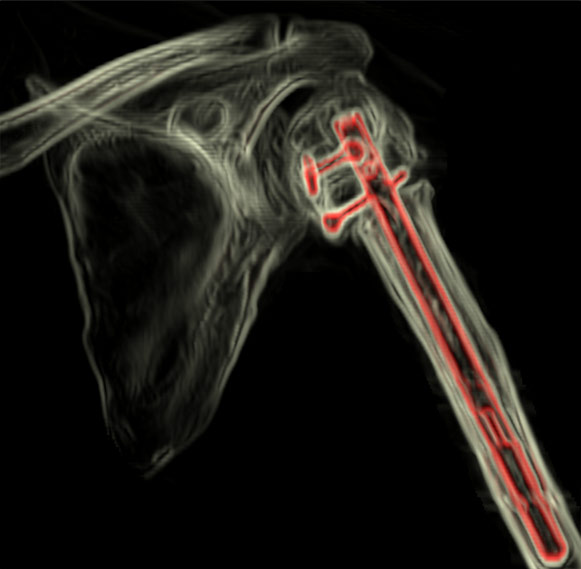

Reconstrucții cu parametri speciali

În cazuri speciale, cum sunt prezența de materialele metalice (tije, șuruburi, proteze), ele vor artefacta imaginea puternic, și de aceea atât protocolul de achiziție, cât și cel de postprocesare sunt puțin diferite. Pentru achiziție se vor utiliza parametri electrici cu valori mai mari și slice foarte fin combinat cu un pitch subunitar, eventual cu modificări ale hărții de afișare a nuanțelor de gri (extended CT scale). Din punct de vedere al postprocesării, reconstrucțiile volumetrice cu evidențierea metalului prin transparența osului sunt foarte utile și ușor de înțeles atât de radiolog cât și de ortoped.

Image

Reconstrucție 3D a humerusului, cu un protocol special care evidențiază ușor metalul prin transparența osului

Rotație în jurul axei – reconstrucţie 3D cu protocol de evidențiere a metalelor